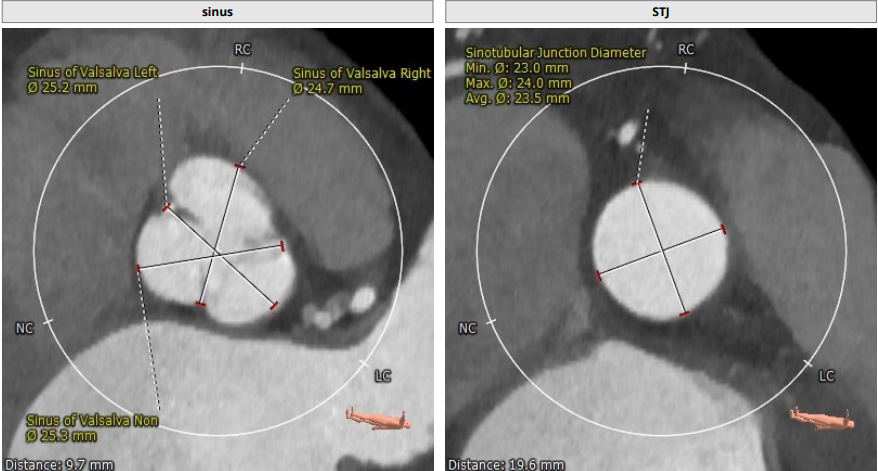

CT评估报告

瓣环平均直径:20.2 mm,左室流出道平均直径:19.9mm

升主动脉(未见)明显扩张,心脏角度:55°

左冠高度:12.5 mm,右冠高度:13.6 mm

Annulus:20.2mm;LVOT:19.9mm

Sinus:25.3mm*25.2mm*24.7mm ;STJ:23mm*24mm

升主:27.6mm*29mm;主动脉成角:55°